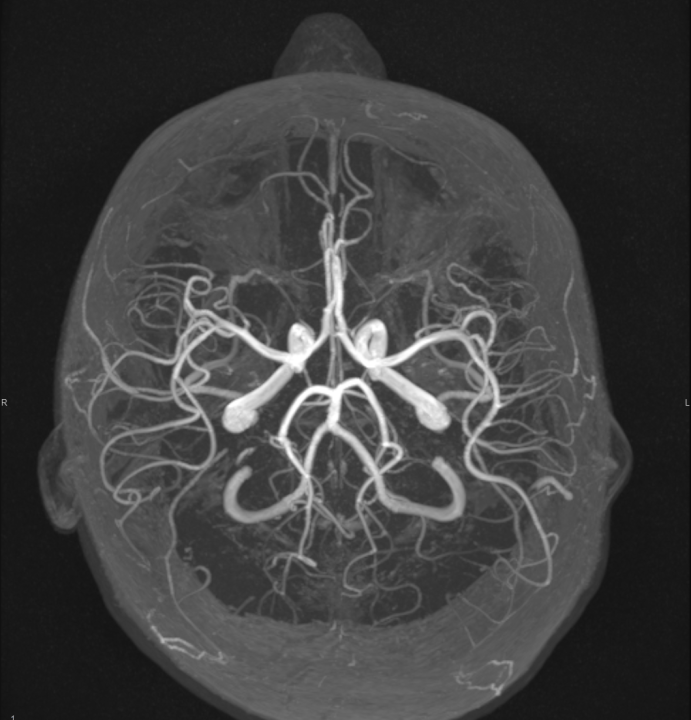

Tijekom Tjedna mozga Poliklinika Affidea Vita daje 20 posto popusta na magnetsku rezonancu!

Povodom obilježavanja Tjedna mozga od 11.

MR angiografija